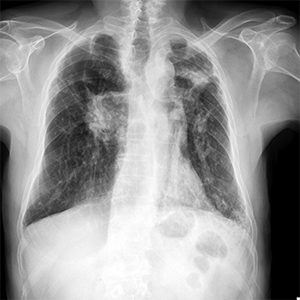

Octubre 2025. Conci Carpinella

Masculino 75 años, APP: TBC, MC: Tos productiva crónica y disnea.